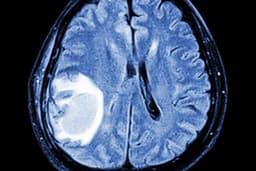

A significant portion of young adults diagnosed with cancer, nearly 10%, eventually develop metastatic disease, meaning their cancer has spread to other parts of the body. This finding comes from a groundbreaking study analyzing data from over 48,000 cancer patients aged 15 to 39. The research indicates that specific cancers, such as sarcoma and colon cancer, are more prone to recurring and spreading, posing a heightened challenge for treatment and survivorship.

This study underscores the serious implications of cancer recurrence in younger populations. Patients experiencing metastatic spread face a threefold higher risk of mortality. While cancer is relatively uncommon in this age group, recent data suggests a concerning rise in certain cancer types among individuals under 50, baffling experts who are exploring various environmental and lifestyle factors.